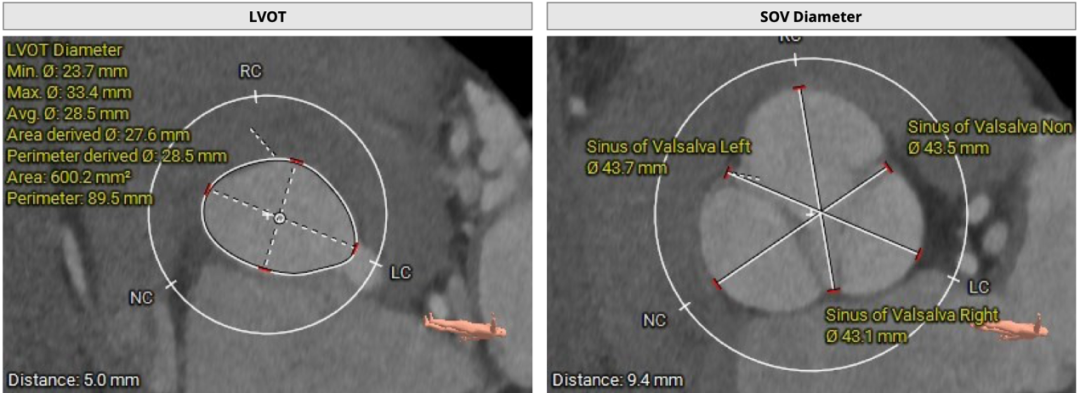

CT分析

主动脉瓣三叶式,瓣叶基本等大,瓣叶稍增厚,瓣叶未见明显钙化。患者主动脉瓣环周长折算直径约26.8mm: